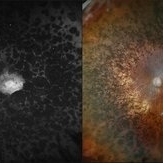

Optomap RGB and AF of an 63-year-old man with secondary pigmentary degeneration of the retina. Patient's Spark genetic testing revealed heterozygous mutations of unknown significance in LRP5, COL18A1, CPLANE1, SLC24A1 and VCAN. Clinical findings most consistent with Wagner's Syndrome (VCAN mutation, autosomal dominant). Will continue follow up care every 6 months with dilated exam and repeat OCT and Optos imaging.

Photographer: Kimberly Wakester, COA, OCT-C

Imaging device: Optos California

Condition/keywords: secondary pigmentary degeneration, Wagner's Syndrome